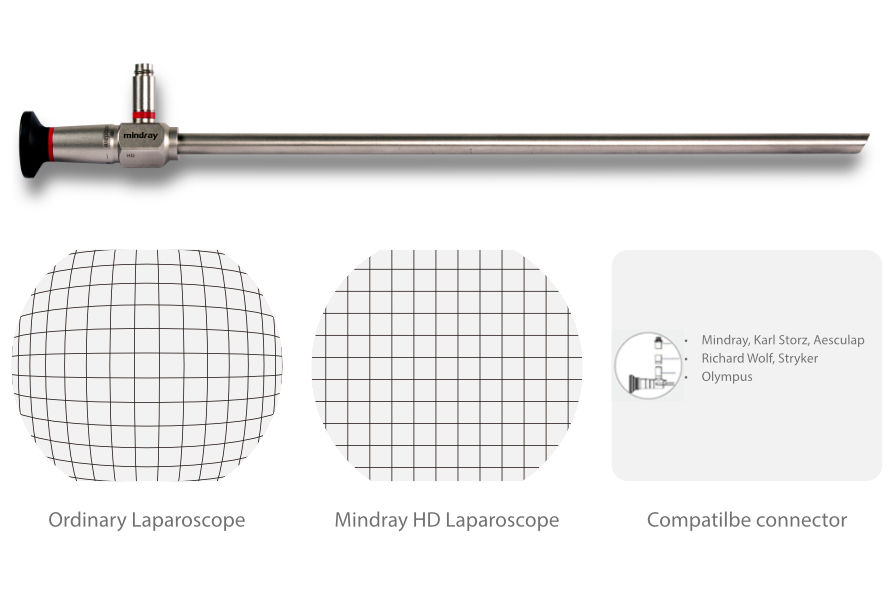

Лапароскопы

- Жесткий эндоскоп M 01030A, входной угол поля зрения объектива 30º

- Жесткий эндоскоп M 01000A,входной угол поля зрения объектива 0º

- Изображения высокого разрешения и улучшенная цветопередача

- Передовые литые асферические линзы для получения четких изображений без искажений

- Встроенная система для компенсации теплового расширения

- Лазерная сварка для надежного уплотнения

- Крышка из сапфирового стекла для защиты оптической системы

- Различные адаптеры оптических портов для подключения оптоволокна

- Пригодность к автоклавной обработке